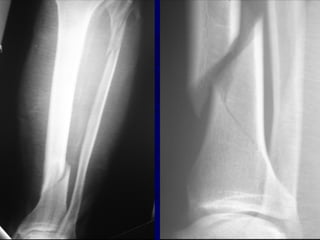

Radiographic Evaluation

• AP and Lat views of entire tib/fib required

from knee to ankle

• Oblique views can be helpful in follow-up

to assess healing